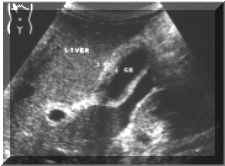

Symmetric

(Picture1)

Picture

1.

Asymmetric